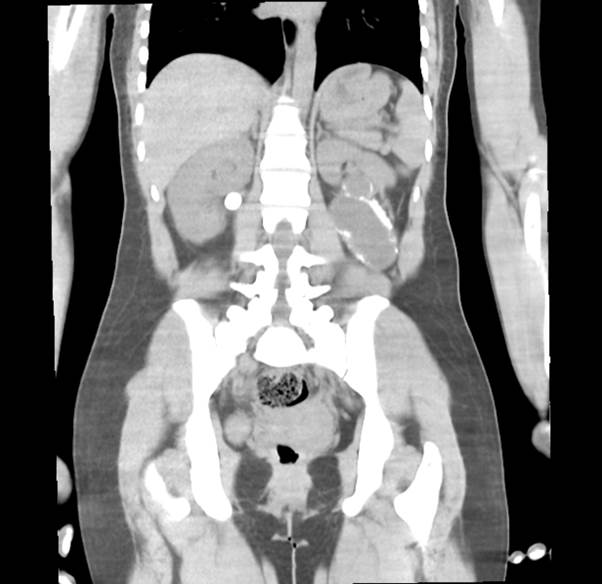

Paciente femenino de 24 años de edad, sin antecedentes de importancia, con presencia de dolor lumbar tipo cólico bilateral de dos años de evolución con irradiación región inguinal, manejado con analgésicos y antiespasmódicos, además de infecciones urinarias de repetición. En enero del 2022 con episodio de dolor importante acudió al servicio de urgencias, donde se solicitó ultrasonido que evidenció pielocaliectasia y litiasis renal derecha, además de quiste renal izquierdo. Se egresa con analgesia y tratamiento antibiótico sin mejoría, por lo que acude al servicio de urgencias de nuestra unidad hospitalaria, donde se realiza urotomografía en la que se observa ectasia pielocalicial derecha así como imagen hiperdensa a este mismo nivel de 16.8x15.4 mm de 780 uh compatible con lito, en polo renal inferior izquierdo se aprecia imagen hipodensa con bordes hiperdensos bien delimitados de aproximadamente 88x67 mm sugerente de quiste renal complejo. En un primer tiempo quirúrgico se realiza ureteroscopia flexible derecha y en un segundo tiempo quirúrgico se programa para realizar destechamiento del quiste renal izquierdo por vía laparoscópica, sin embargo, durante el transoperatorio se evidencia presencia de doble sistema colector con exclusión renal parcial izquierda secundaria por lo que se procede a realizar nefrectomía parcial (Imágenes 1, 2 y 3).

Imagen 1 TAC Simple corte coronal: presencia de imagen quística con paredes calcificadas dependiente de polo renal inferior de unidad renal derecha